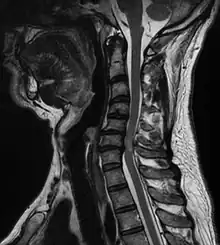

| A tumour causing spinal cord compression | |

Diagnosis is by X-rays but preferably magnetic resonance imaging (MRI) of the whole spine.[3][4]